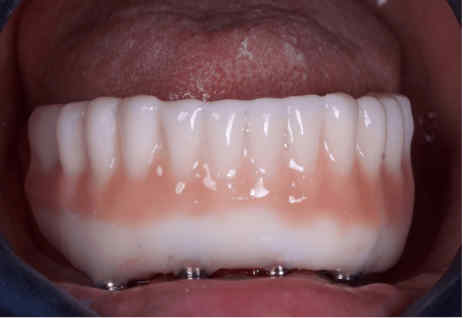

The provisional prosthesis was directly relined and secured using titanium abutments and flowable resin (Figures 9, 10). The installation of the temporary prosthesis for immediate loading was performed (Figure 11). The final panoramic radiograph and tomography image showing the result was obtained, revealing the implant placement with immediate provisional fixed rehabilitation (Figures 12, 13).

FIGURE 11: Installation of the temporary prosthesis for immediate loading

FIGURE 13: Final occlusion – frontal view